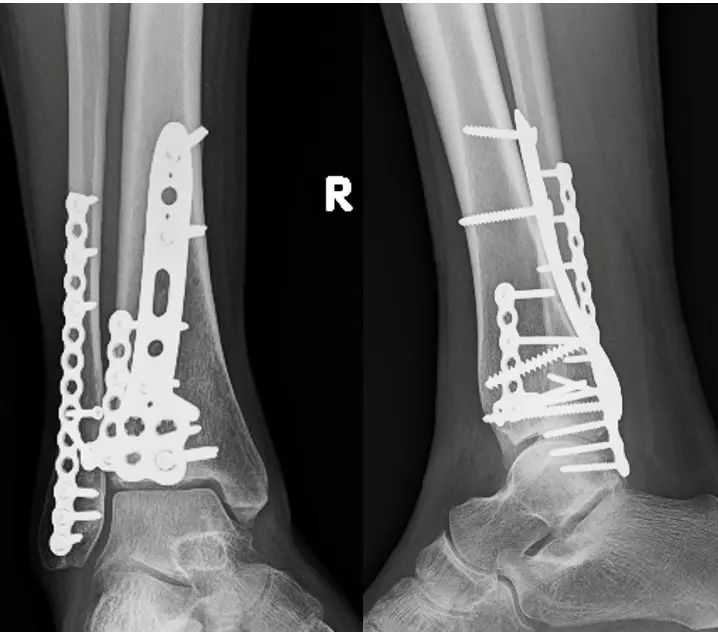

Treatment Imaging

Fracture Care